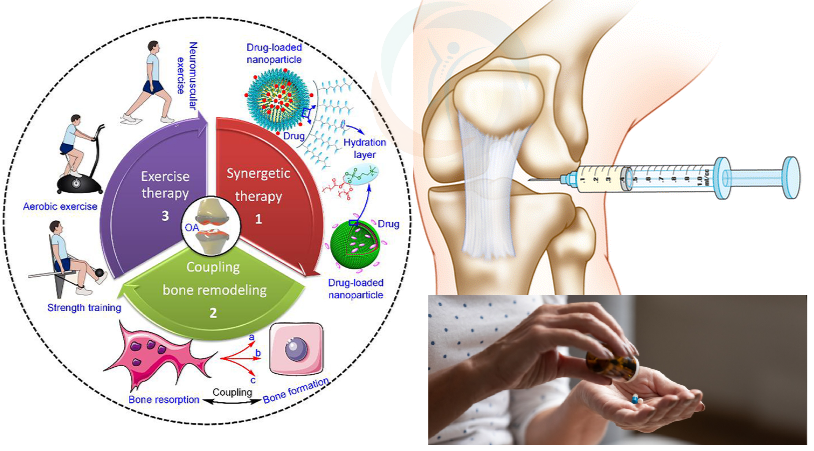

درمان توانبخشی برای آرتروز زانو

توانبخشی برای آرتروز زانو شامل مجموعه ای از تمرینات و مداخلات درمانی است که به کاهش درد، بهبود حرکت و افزایش قدرت عضلات اطراف زانو کمک میکند. هدف اصلی توانبخشی، کاهش فشار روی مفصل آسیب دیده، افزایش ثبات زانو و بهبود عملکرد روزمره است. این برنامه ها معمولاً شامل تمرینات کششی، تقویتی، اصلاح وضعیت بدنی و آموزش روش های محافظت از زانو در فعالیت های روزانه می باشند. همچنین درمانگر ممکن است از روش های کمکی مانند گرما، سرما و الکتروتراپی برای کاهش التهاب و درد استفاده کند. توانبخشی منظم و صحیح میتواند کیفیت زندگی افراد مبتلا به آرتروز زانو را به طور چشمگیری بهبود بخشد.

ورزش آرتروز زانو

مطالعات علمی از مزایای حرکات ورزشی، حتی اگر در منزل باشد، بر درد و عملکرد بیماران مبتلا به استئوآرتریت زانو پشتیبانی می کنند.

ورزش های زانو

ورزش های زانو بخش مهمی از درمان و پیشگیری از مشکلات مفصلی به شمار میآیند و در بسیاری از بیماران بهعنوان خط اول درمان توصیه میشوند. در این تمرینات تأکید ویژهای بر تقویت عضله چ هارسر ران وجود دارد، زیرا این عضله نقش کلیدی در پایداری مفصل زانو و کاهش فشار وارد بر آن ایفا میکند. ورزشدرمانی زانو نهتن ها موجب تقویت عضلات اطراف مفصل میشود، بلکه به بهبود دامنه حرکتی، کاهش درد و افزایش کیفیت زندگی بیماران نیز کمک میکند.

ورزش های هوازی مناسب آرتروز زانو

ورزش هوازی درد و حساسیت مفاصل را کاهش داده و وضعیت عملکرد و ظرفیت تنفسی را ارتقا میبخشد. این نوع ورزش تحمل فعالیت و آستانه درد را افزایش داده و میتواند بر خلق و خو و انگیزه برای مشارکت در سایر فعالیت ها تأثیر مثبت بگذارد.

در حالی که ورزش تقویتی زانو در کوتاه مدت برای نتایج خاص (مانند درد) بر ورزش هوازی برتر است، تمرین هوازی برای نتایج عملکردی در دراز مدت مؤثرتر است.